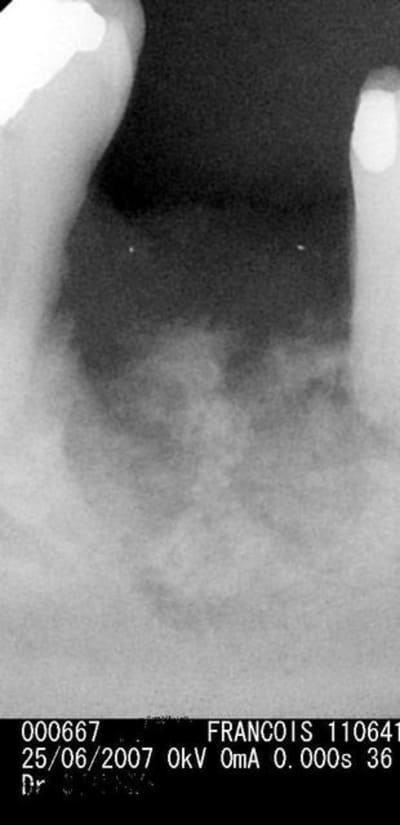

et une nécrose aprés extraction sous zometa, j'avais demandé l'avis du Prof qui avait donné son autorisation; méfiance donc avec ce type de traitement

Aucun traitement à ce jour. Pas d'implants et ne toucher à rien, pas d'extractions. Images impressionnantes de désastres osseux.